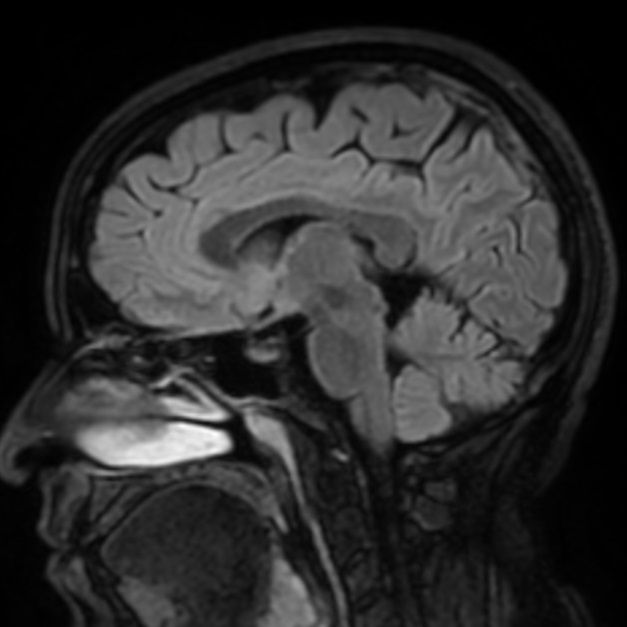

L’Imagerie par Résonance Magnétique est une technique qui analyse les organes de votre corps en utilisant un aimant très puissant.

Cet aimant forme l’essentiel de l’appareil. La combinaison des énergies délivrées par cet appareil permet de détecter le signal émis par les atomes d’hydrogène contenus dans les organes.

Le signal émis par ces atomes est enregistré par une antenne située au contact de la zone à étudier. Ce signal est ensuite traité par un ordinateur qui réalise

des images en coupes de votre corps. Les images sont affichées sur un écran. Elles peuvent ensuite faire l’objet d’un traitement informatique appelé «